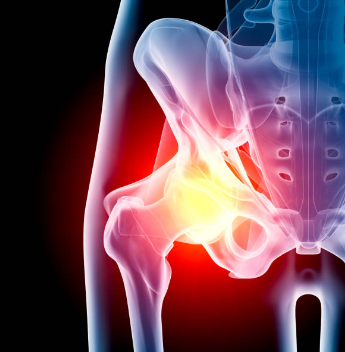

고관절 수술

고관절 수술은 주로 고관절의 통증과 기능 장애를 완화하기 위해 시행됩니다. 고관절 수술에는 여러 가지 방법이 있으며, 주로 다음과 같은 경우에 시행됩니다.

고관절 골절

고관절 골절은 특히 고령자에게 흔히 발생하며, 수술을 통해 골절 부위를 고정하거나 인공관절로 대체합니다.

고관절염

고관절의 염증이나 퇴행성 변화로 인해 통증이 심해질 경우, 인공관절 치환술을 통해 통증을 완화하고 기능을 회복할 수 있습니다.

대퇴골두 무혈성 괴사

대퇴골두로의 혈액 공급이 차단되어 뼈 조직이 괴사하는 경우, 인공관절 치환술이 필요할 수 있습니다.

고관절 수술의 종류

내고정술

나사나 금속 정을 이용해 골절 부위를 고정하는 방법입니다. 주로 골두를 보존할 수 있는 경우에 사용됩니다.

인공관절 치환술

손상된 고관절을 제거하고 인공관절로 대체하는 수술입니다. 이 수술은 통증을 완화하고 관절의 기능을 회복시키는 데 효과적입니다.